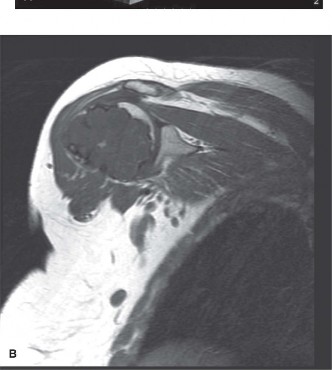

A 61-year-old female with several months of deep pain in the right shoulder is

referred to you by her primary care physician. She presents to your office with the radiographs and an MRI is obtained (Fig. 8–17A–C).

Figure 8–17 A–B

Which of the following is true regarding the lesion shown inFigure 8–17A–C. 1. Needle biopsy is not as accurate in determining the grade as in other tumors

The correct answer is (A). Chondrosarcoma is a malignant cartilage-producing tumor. Three grades exist, in addition to a dedifferentiated form, and histopathologic examination of these lesions is not as reliable predictor of grade as in other lesions. For this reason, evaluation of the imaging is critical in determining the appropriate management. Location is important to the diagnosis of these lesions; for example, lesions in the hand are most commonly benign enchondromas, while those in the scapula are more commonly malignant. These tumors have little or no sensitivity to chemotherapy and radiation; therefore surgical resection is the primary treatment. For grade 1 lesions of the extremities, which are locally aggressive but have limited, if any, potential to metastasize, intralesional curettage and bone grafting is an accepted treatment with low recurrence rate. Pelvis lesions of any grade generally have a poorer prognosis, so wide resection is preferred in